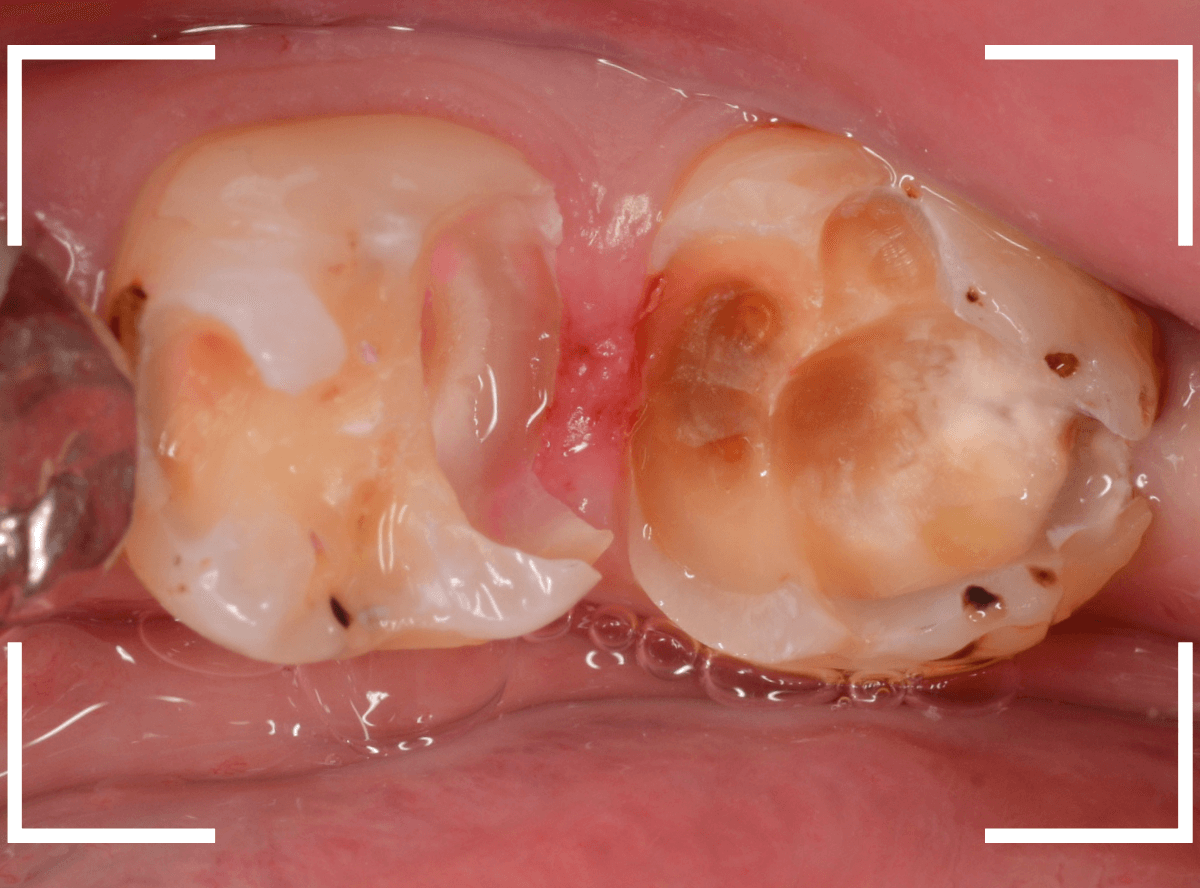

Case.1 隣り合った2本が大きな虫歯

「下の歯の奥から2番目の歯が痛む」という患者さんです。

お口の中を拝見すると、何だか1番奥の歯も怪しそうなので、歯を叩いて症状を確認してみます(打診)。

やっぱり奥から2番目の歯が痛むけど、1番奥の歯も少し痛むそうです。

レントゲン写真で確認してみました。

やはりどちらの歯も大きな虫歯でした。

まずは、麻酔をしてつめ物を慎重に外してみます。

両歯とも、色々嫌な予感のする所見です。

虫歯を可視化する、「う蝕検知液」で染め出ししてみます。

赤く染まっている場所が虫歯で、濃く染まっているところほど、虫歯は深いです。

手前の歯は一部神経が見えそうなところまで虫歯が来ていました(●部)。

患者さんのおっしゃるように、この歯が痛みの原因だったのかもしれません。

後ろの歯も、幸い神経は見えていませんが、かなり広く深い虫歯で心配な状況です。

急いで、神経を保護する薬を入れた後に、セメントで蓋をして経過観察します。

ほとんどの方はこれで何とかなりますが、痛みが出てしまい、神経の治療が必要になる方もいます。

神経の治療をすると歯の寿命は短くなってしまうので、できるだけ避けたいところです。

慎重に経過観察します。